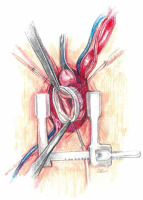

Central cannulation is performed as the first choice. Heparin is administered at a dose of 3 mg/kg body weight intravenously titrated to the activated clotting time higher than 450 s. In the area of the brachiocephalic trunk, two Ti-Cron 2-0 purse - string sutures are applied. The aorta is cannulated using an EOPA cannula (Medtronic Inc, Minneapolis, MN, USA) and airlessly connected to the extracorporeal artery line. Venous outflow is provided by insertion of an MC2X two-stage cannula (Medtronic, Inc) into the right atrium. The cannula is then pulled out of the chest under the sternum through a small handrail under the xiphoid process, through which the chest tube is carried out after the surgery (Figure 4). At this stage, it is possible to start extracorporeal circulation. With the emptied heart, a 16 F vent (Medtronic Inc, Minneapolis, MN, USA) is inserted through the right superior pulmonary vein into the left atrium. The patient’s body temperature is maintained at 34°C.

At low flow, a transverse clamp is placed on the border of the distal part of the ascending aorta and the brachiocephalic trunk. The aorta is opened transversely and cold Custodiol (Essential Pharmaceuticals, LLC, Durham, NC) cardioplegia is administered directly to the coronary ostia at a single dose [5]. First, the coronary orifices are excised and the tissue surrounding the initial epicardial course of the coronary arteries is mobilized. Prolene 4-0 mattress sutures are placed on each prepared “button” for gentle traction and improved exposure. After mobilization of the openings, the coronary sinuses are excised, leaving a tissue margin of several millimeters just above the aortic annulus. Ti-Cron 2-0 pledgeted sutures are placed on each prepared commissure (Figure 5) for better exposure. Mosquito forceps are fixed at the ends of the seams providing gentle traction. This simple movement significantly improves visibility in the operating field. At the next stage, the length of the leaflets the height of the commissures are measured and the size of the “neo-root” is selected. The aortic annulus is measured with valve gauges for mechanical prostheses. All measurements taken at this stage are crucial because on their basis the aortic root will be reconstructed. Graft sizing is based on the height of the commissure between the left and the noncoronary sinuses. The height is measured with a ruler from the base of the interleaflet triangle to the top of the commissure, because this measurement corresponds to the size of the graft that will be used. Ethibond 2-0 ring sutures are placed horizontally from the left ventricle aspect to the outside of the aortic annulus. Placing them tightly next to each other, in a tiled shape, helps to stabilize the annulus. After selecting the size of the aortic graft, the sutures are placed successively on the aortic prosthesis and tied to the annulus. In general, straight prostheses are used (Hemashield Platinum Woven Double Velour, Getinge AB, Göteborg, Sweden). In the next stage, the aortic root is trimmed inside the neo-root (Figure 6). Previously performed measurements are used to properly arrange the height of the commissures and leaflets on the wall of the aortic prosthesis. With the Prolene 5-0 suture, the commissures within the margin of the aortic annulus are sewn to the prosthesis. Sewing starts from the nadir of the commissure and goes up towards to the top. In the next step, the competence of the valve and the coaptation of the leaflets are checked in saline testing. If necessary, repair of the valve leaflets is performed at this time. In the aortic prosthesis, at the height of the Valsalva sinuses, round holes for the coronary ostia are excised. The distance to the holes is determined on the temporarily unvented left ventricle to prevent kinking of the coronary vessels when the aortic clamp is removed. The parachute technique uses the Prolene 5-0 suture to sew the left and then the right coronary ostia (Figure 7). In the last stage, the trimmed distal part of the prosthesis is fixed to the aortic arch with the Prolene 5-0 suture. The suturing of the anastomosis begins on the posterior wall of the aorta, heading initially towards the pulmonary trunk and then towards the operator. Before the anastomosis is completed, the heart is vented and the aortic clamp is removed. De-airing of the heart is performed using the anti-Trendelenburg position, filling the lungs and heart, and an active vent from the left ventricle. After the distal anastomosis is closed, the patient is heated to normothermia.